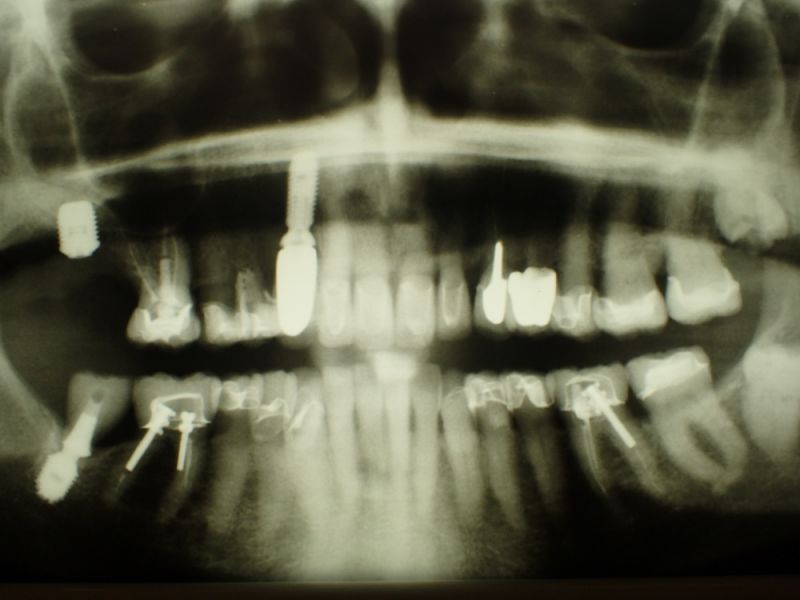

80 jährige rekonstruierte CMD Patientin erhält ein Implantat

Bei der 80 jährigen Patientin wurde heute in regio 17 ein Implantat inseriert, mit dem Ziel der Wiederherstellung der linken Stützzone.

Wie man beispielhaft an diesem Fall sehen kann, geht der Trend in die Richtung selbst Patienten im fortgeschrittenen Alter weiter mit festsitzendem Zahnersatz zu versorgen, wenn der Patient das in der Vergangenheit so gewohnt war.